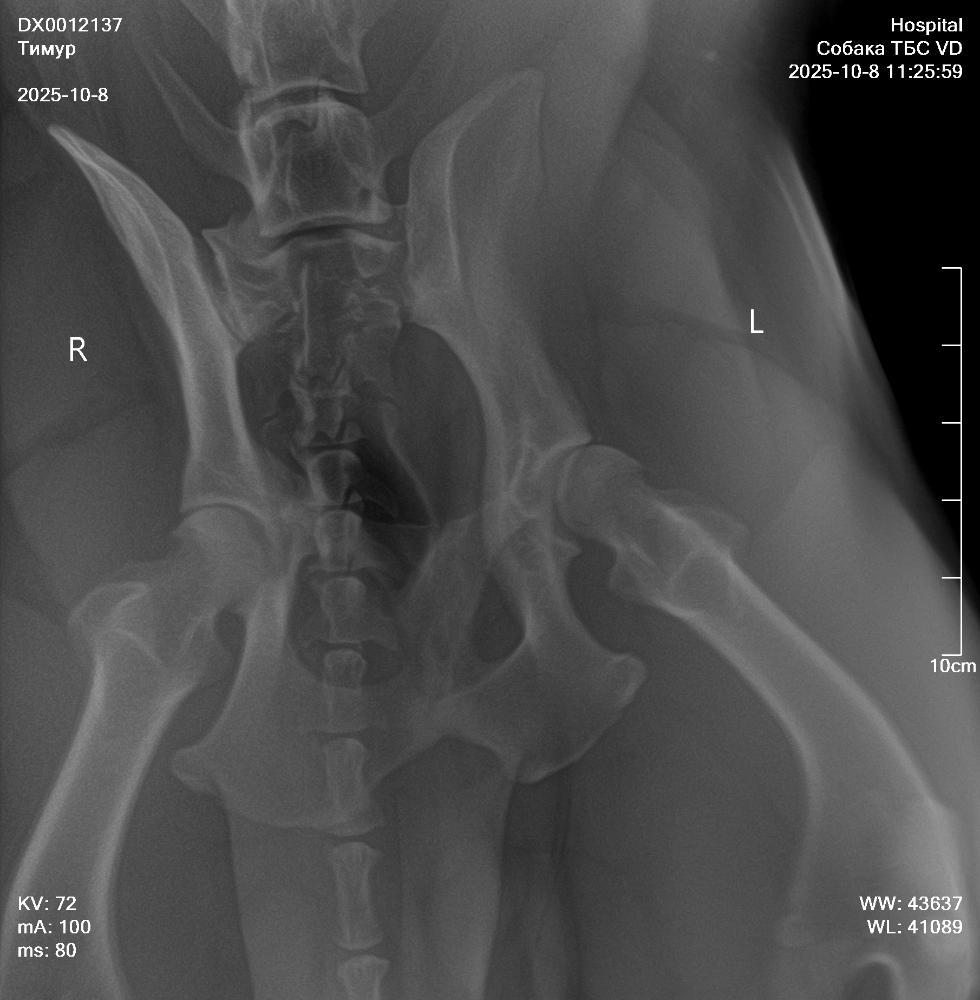

NataP Опубликовано 8 октября, 2025 Опубликовано 8 октября, 2025 Здравствуйте. Три дня назад после прогулки Тимур захромал, хотя сильных нагрузок не даём, немного поиграли с пуллером. Сегодня създили в клинику, сделали снимки без седации, кое как смогли завалить, сопротивлялся, поэтому снимки получились не такие, как хотелось бы. Но даже по ним нам ставят дисплазию и рекомендуют операцию по протезированию. Хочу проконсультироваться онлайн в Москве. Посоветуйте, пожалуйста, где сейчас лучше консультироваться, и подойдут ли такие снимки, или лучше переделать под седацией. Сейчас пока выписали онсиор или робексеру на 10 дней, но Омез сказали, давать не нужно, а я сомневаюсь, может всё-таки давать? Простите за много букв, просто в панике пока, а кроме вас не к кому обратиться. Снимки прикрепила.

Кирюша и Маруся Опубликовано 9 октября, 2025 Опубликовано 9 октября, 2025 Снимки без седации полная дезинформация. А к врачам, которые делают их для постановки диагноза лучше не ходить. Сделайте нормальные снимки с седацией у профи. При сомнении и пон азначению врача - МРТ. А обезбол крупной моложой собаке на травированную связку - это странно, так как нужно граничивать движение, а не просто снимать болевой и давать скакать. По врачам в МСК: Мезин, Еремин, Ягников, Воронцов, Самошкин, Середа, Давыдов, Гранин... Выбирайте любого. Нормальные рентгены делают они все. 1

NataP Опубликовано 9 октября, 2025 Автор Опубликовано 9 октября, 2025 То есть эти снимки вообще безполезны? Зря только с Тимуром воевали, чтоб на стол уложить(

Звезда Севера Опубликовано 9 октября, 2025 Опубликовано 9 октября, 2025 К сожалению, да. Такие снимки не информативны. Я так понимаю, что вам ближе в Нижний Новгород ехать? Может, там найти хороших специалистов?